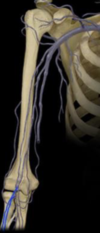

vascularisation du membre supérieur, thorax et abdomen Flashcards